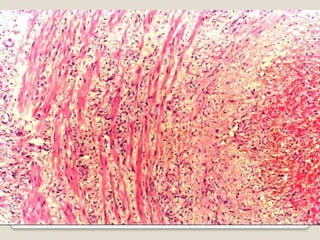

 Involved arteries have nodular thickening

reduction of lumenthrombosis.

Granulomatous inflammation in inner half of

media with mononuclear cells+ giant cells.